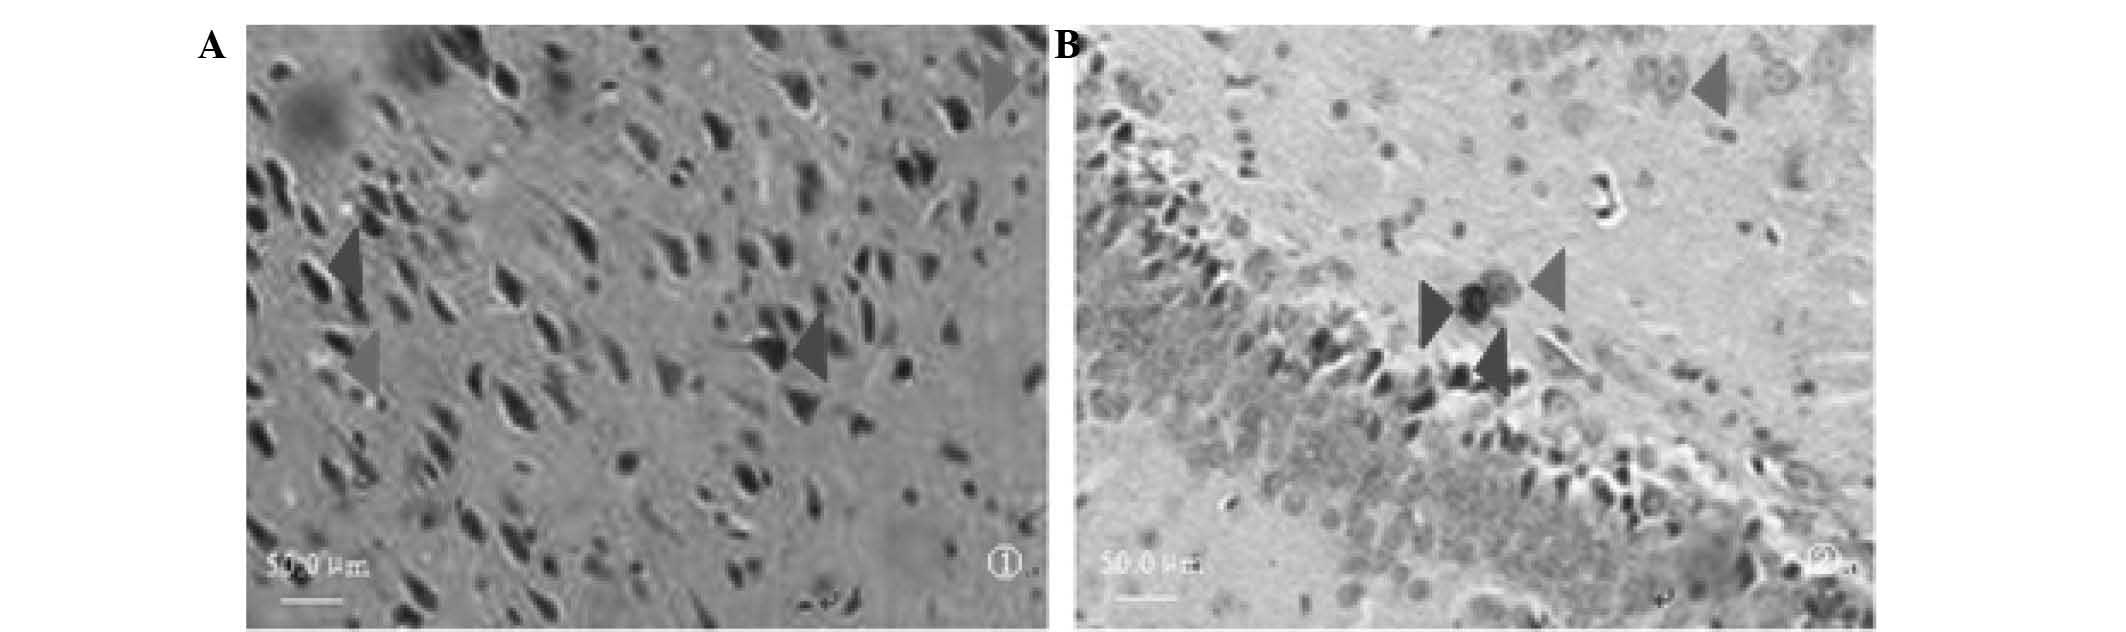

Effects of apoptosis‑related proteins caspase‑3, Bax and Bcl‑2 on cerebral ischemia rats

Neuron apoptosis is known to mediate a change of ethology following cerebral ischemia̸reperfusion injury in rats. Additionally, Bcl‑2, Bax and caspase‑3 proteins may exert a significant effect on neuron injury. The aim of this study was to investigate the role, mechanism of action and clinical significance of these proteins in neuron apoptosis and functional impairment following cerebral ischemia̸reperfusion injury in rats. Sixty male healthy adult Wistar rats were randomly assigned into control (n=6), sham operation (n=6) and experimental (n=48) groups. The model of rat cerebral ischemia̸reperfusion injury was set up according to the method of Zea‑Longa. Eight subsets of 6 rats̸subset were designed according to time points (at 3, 6, 12, 24 and 48 h and at 3, 7 and 14 days). Nerve functional injury was evaluated and graded using nerve function score, balance, coordination function detection and measurement of forelimb placing. The neurons expressing caspase‑3, Bax and Bcl‑2 in the cortical area, CA3, CA1, stratum lucidum (Slu) and molecular layer of the dentate gyrus (MoDG) of the hippocampus were detected using immunohistochemistry or the TUNEL method. The expression of caspase‑3, Bax and Bcl‑2 genes was detected by the reverse transcriptase polymerase chain reaction (RT‑PCR). The results indicated that, compared to the sham operation group, the score of nerve function and balance beam walking were distinctly higher (P<0.01) and the percentage of rat foreleg touching the angle or margin of the table was significantly lower in the experimental rat group (P<0.01) at 3 h following reperfusion. The expression of TUNEL‑positive neurons was high in the cortical area and the CA3 region of the hippocampus (P<0.01), caspase‑3 was at peak value in the cortical area and the CA1 region of the hippocampus (P<0.01), Bax was increased in the cortical area and the Slu of the hippocampus (P<0.01) and Bcl‑2 was low in the cortical area and the MoDG of the hippocampus (P<0.01) in the experimental group at 48 h following reperfusion. In conclusion, cerebral ischemia/reperfusion injury may cause neurological impairment and lead to a change of ethology, and neuron apoptosis may be associated with the activation of caspase‑3 and Bax and the downregulation of Bcl‑2.